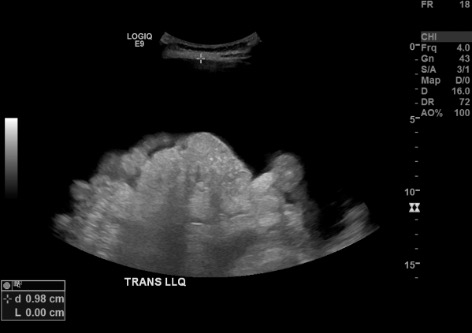

US survey — LLQ fluid pocket + Doppler

Color Doppler US of LLQ showing vessel check at planned paracentesis access site B-mode US measuring distance from skin to ascitic fluid pocket in LLQ B-mode US confirming no vessels along needle trajectory in LLQ